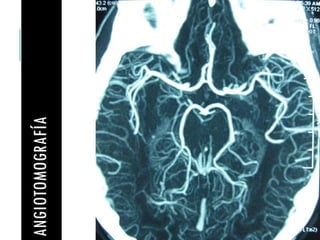

ANGIOTOMOGRAFÍA

Angiografía por TC Sensibilidad baja